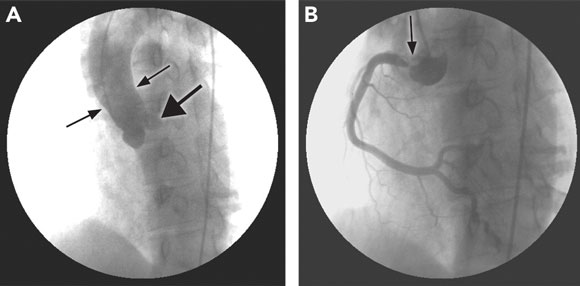

A coronary angiogram revealed a completely occluded left main coronary artery at the ostium, and a 90% ostial lesion of his right coronary artery; the remainder of his right coronary system was clear of disease (Figure 2). He underwent emergency coronary artery bypass grafting. The operative notes do not comment on the appearance of the native coronary arteries, nor were these sent for histological examination. An aortic wall biopsy showed mild degenerative changes only — syphilis could not be excluded as causing these changes. In view of the bilateral coronary ostial lesions, syphilis serology was performed.

2 Coronary angiograms of Patient 2  \ \

A: Tapering of the aortic root (thin arrows) and left main coronary stump (arrowhead). |